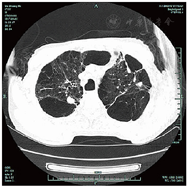

共317例TOPD患者完成影像学检查。TOPD患者肺部CT显示多处钙化结节等结核瘢痕,部分患者存在一定程度的肺气肿和支气管扩张征象,见图1,图2,图3。TOPD患者左肺上、舌、下叶的结核瘢痕阳性分别为176例(55.5%)、120例(37.9%)和126例(39.7%),右肺上、中、下叶的结核瘢痕阳性分别为215例(67.8%)、142例(44.8%)、168例(52.9%);左肺的支气管扩张征象主要集中在左肺舌叶,右肺主要位于中叶、下叶;肺气肿在双肺间分布较为均衡,见图4。

注:患者男,双上肺见多发散在斑片状钙化灶及索条影,双肺内见散在无壁空腔影,双肺胸膜下可见多发网格状阴影及肺大泡影